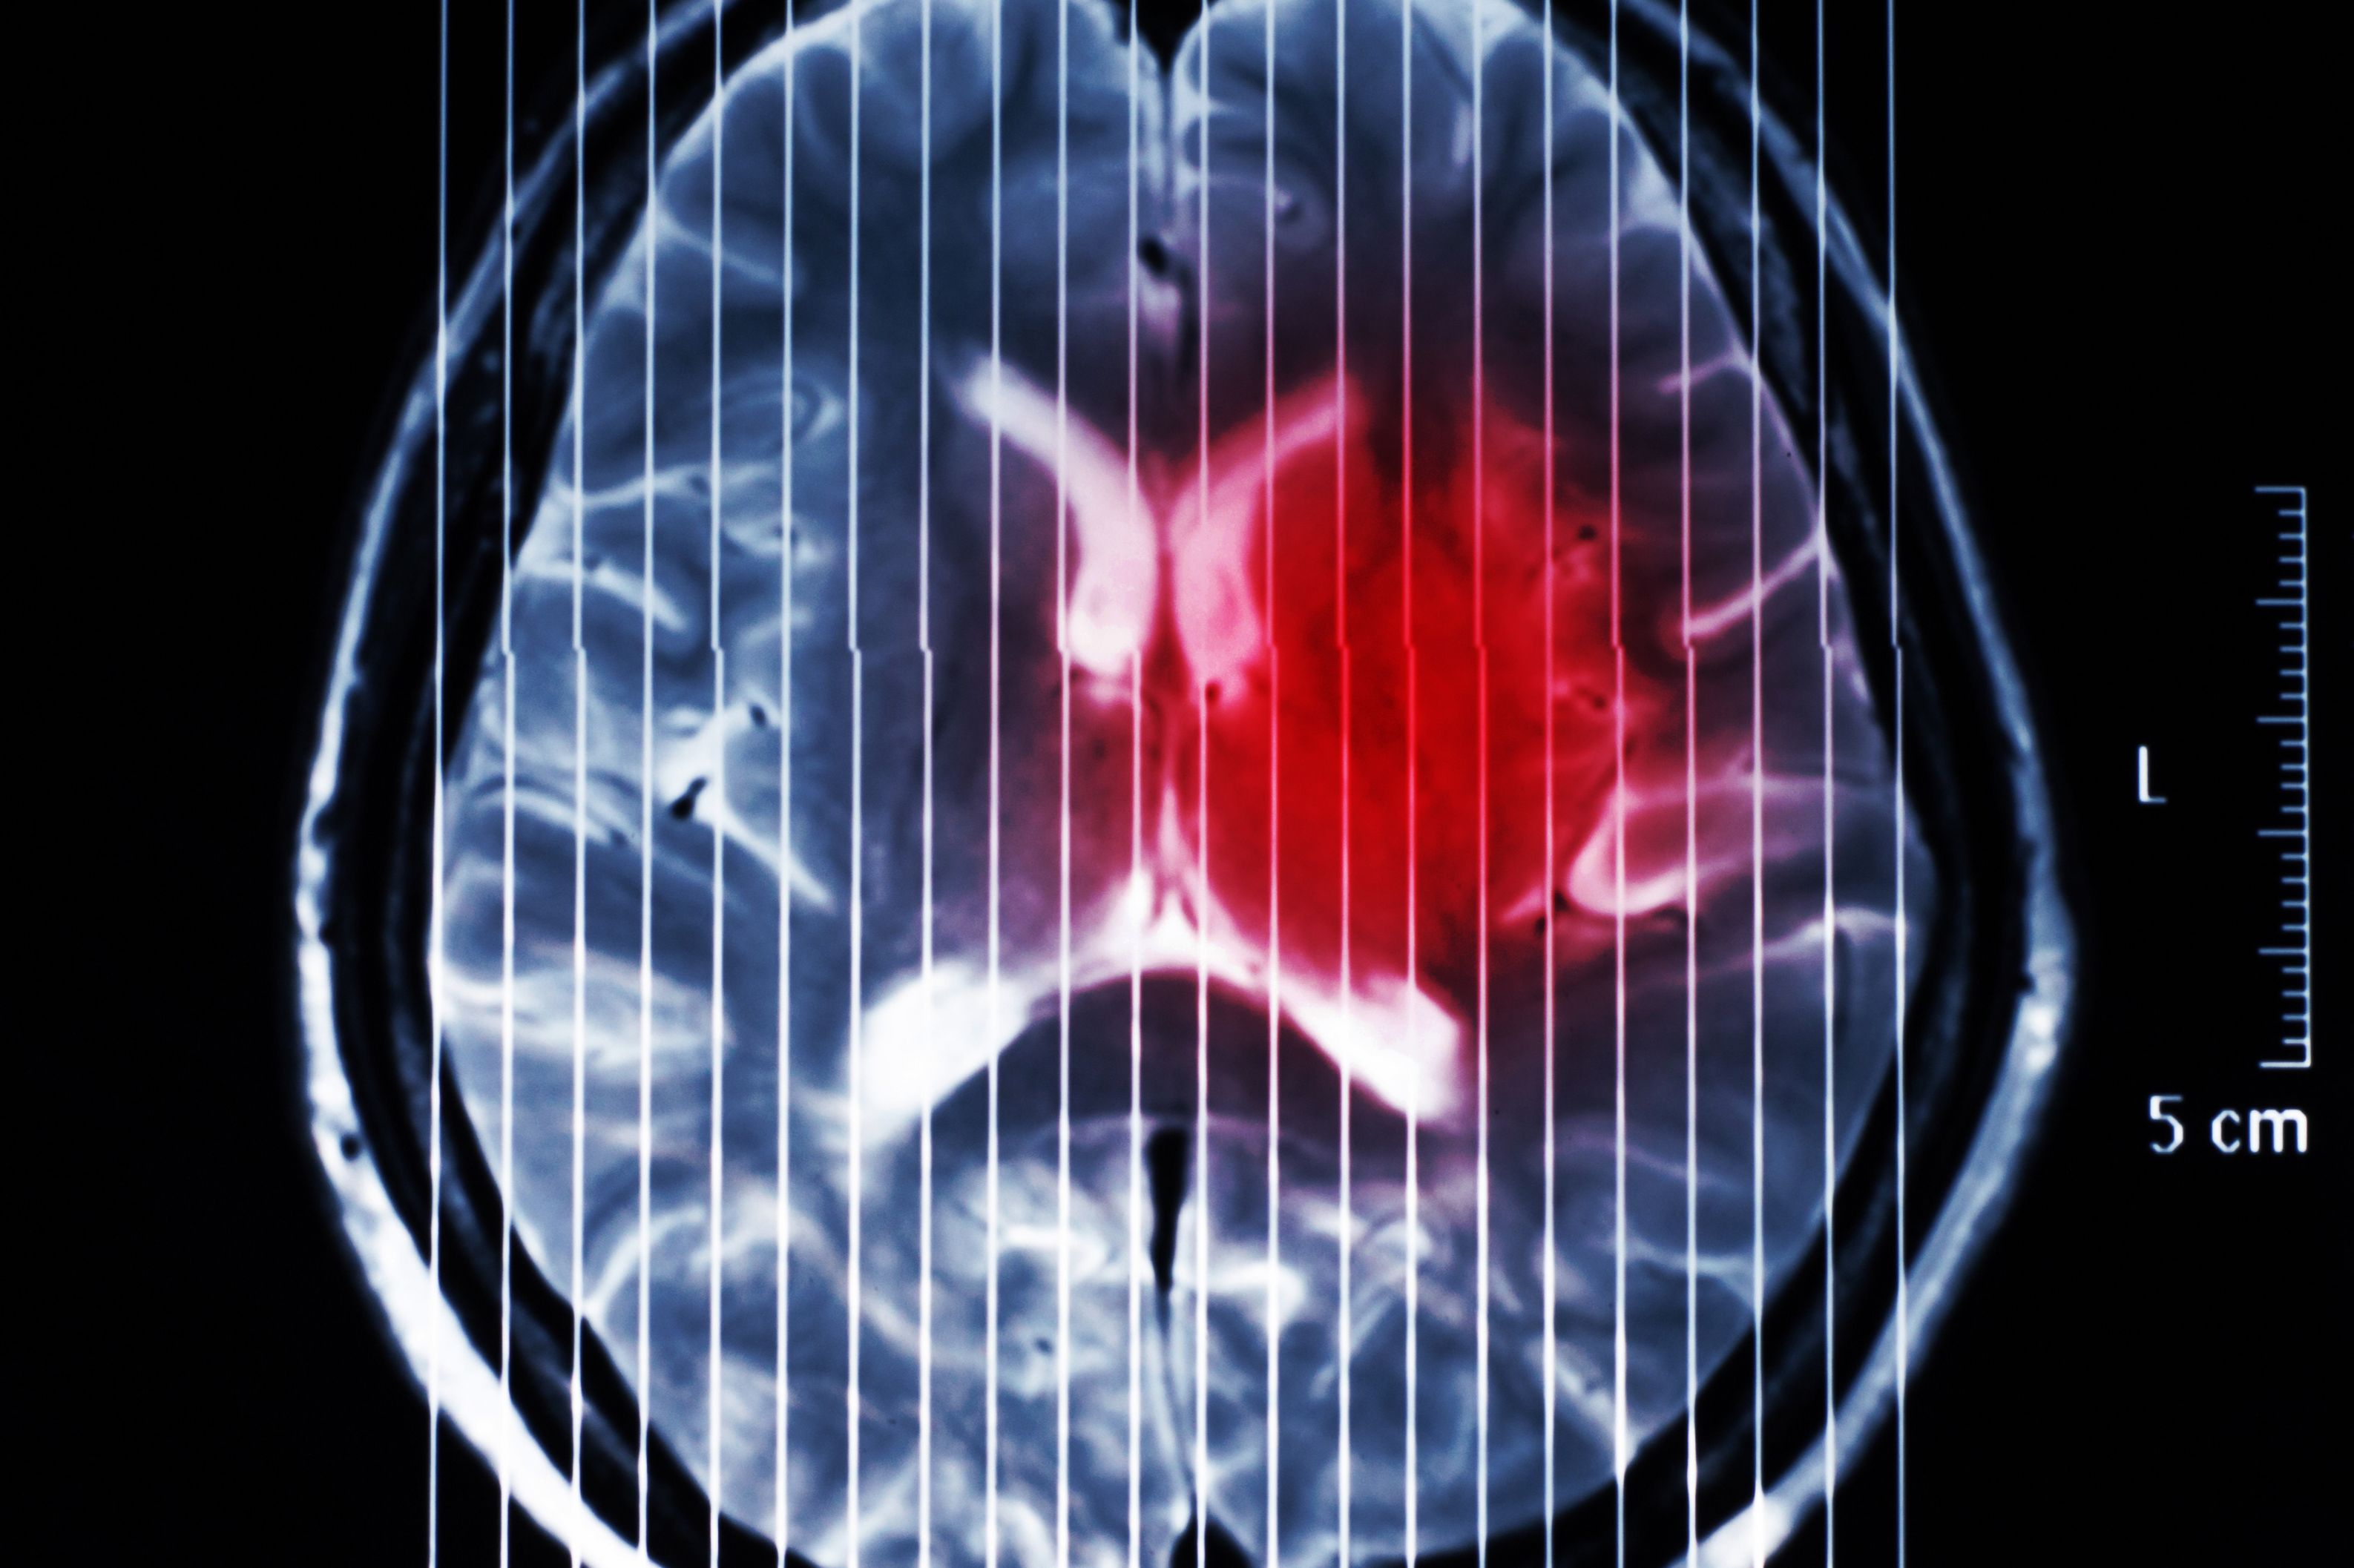

(Vienna, 17 December 2024) Diffuse hemispheric glioma (DHG) is a brain tumor in children, adolescents and young adults with an average survival prognosis of less than two years and limited treatment options. A research team from MedUni Vienna and University Hospital Vienna has identified increased stress through targeted DNA breaks with simultaneous inhibition of DNA repair in the tumor cell as a promising therapeutic approach. The study has just been published in the journal "Neuro-Oncology".

The underlying molecular mechanisms of DHG were first characterized a good ten years ago. Due to these specific characteristics, DHG is now listed as an independent brain tumor type. However, it has not yet been possible to translate this knowledge into more efficient treatment options. The current research work led by Johannes Gojo (Department of Pediatrics and Adolescent Medicine) and Walter Berger (Center for Cancer Research) was able to show that the tumor cells use a special mechanism to become "immortal". However, this mechanism is associated with elevated stress due to increased damage to genetic material (DNA). The research group identified this "vulnerability" as a new therapeutic approach and showed that the targeted triggering of further DNA damage with simultaneous inhibition of DNA repair represents a promising therapeutic approach for this aggressive type of brain tumor.